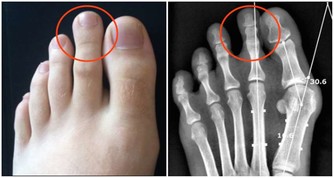

1、觀察自己的雙手,如果發現指尖比指節更粗大,可能是患有較嚴重的肺部疾病;